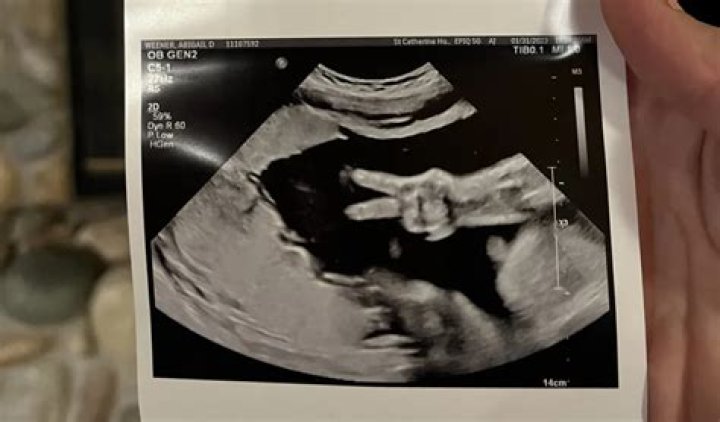

Halsey Proudly Shows Off Her Growing Baby With An Adorable Ultrasound Of Her Unborn Child’s Feet

Halsey took to Instagram to share an eye-catching new photo of what looks like her baby’s feet in a clear ultrasound pic that tagged her doctor and it had...